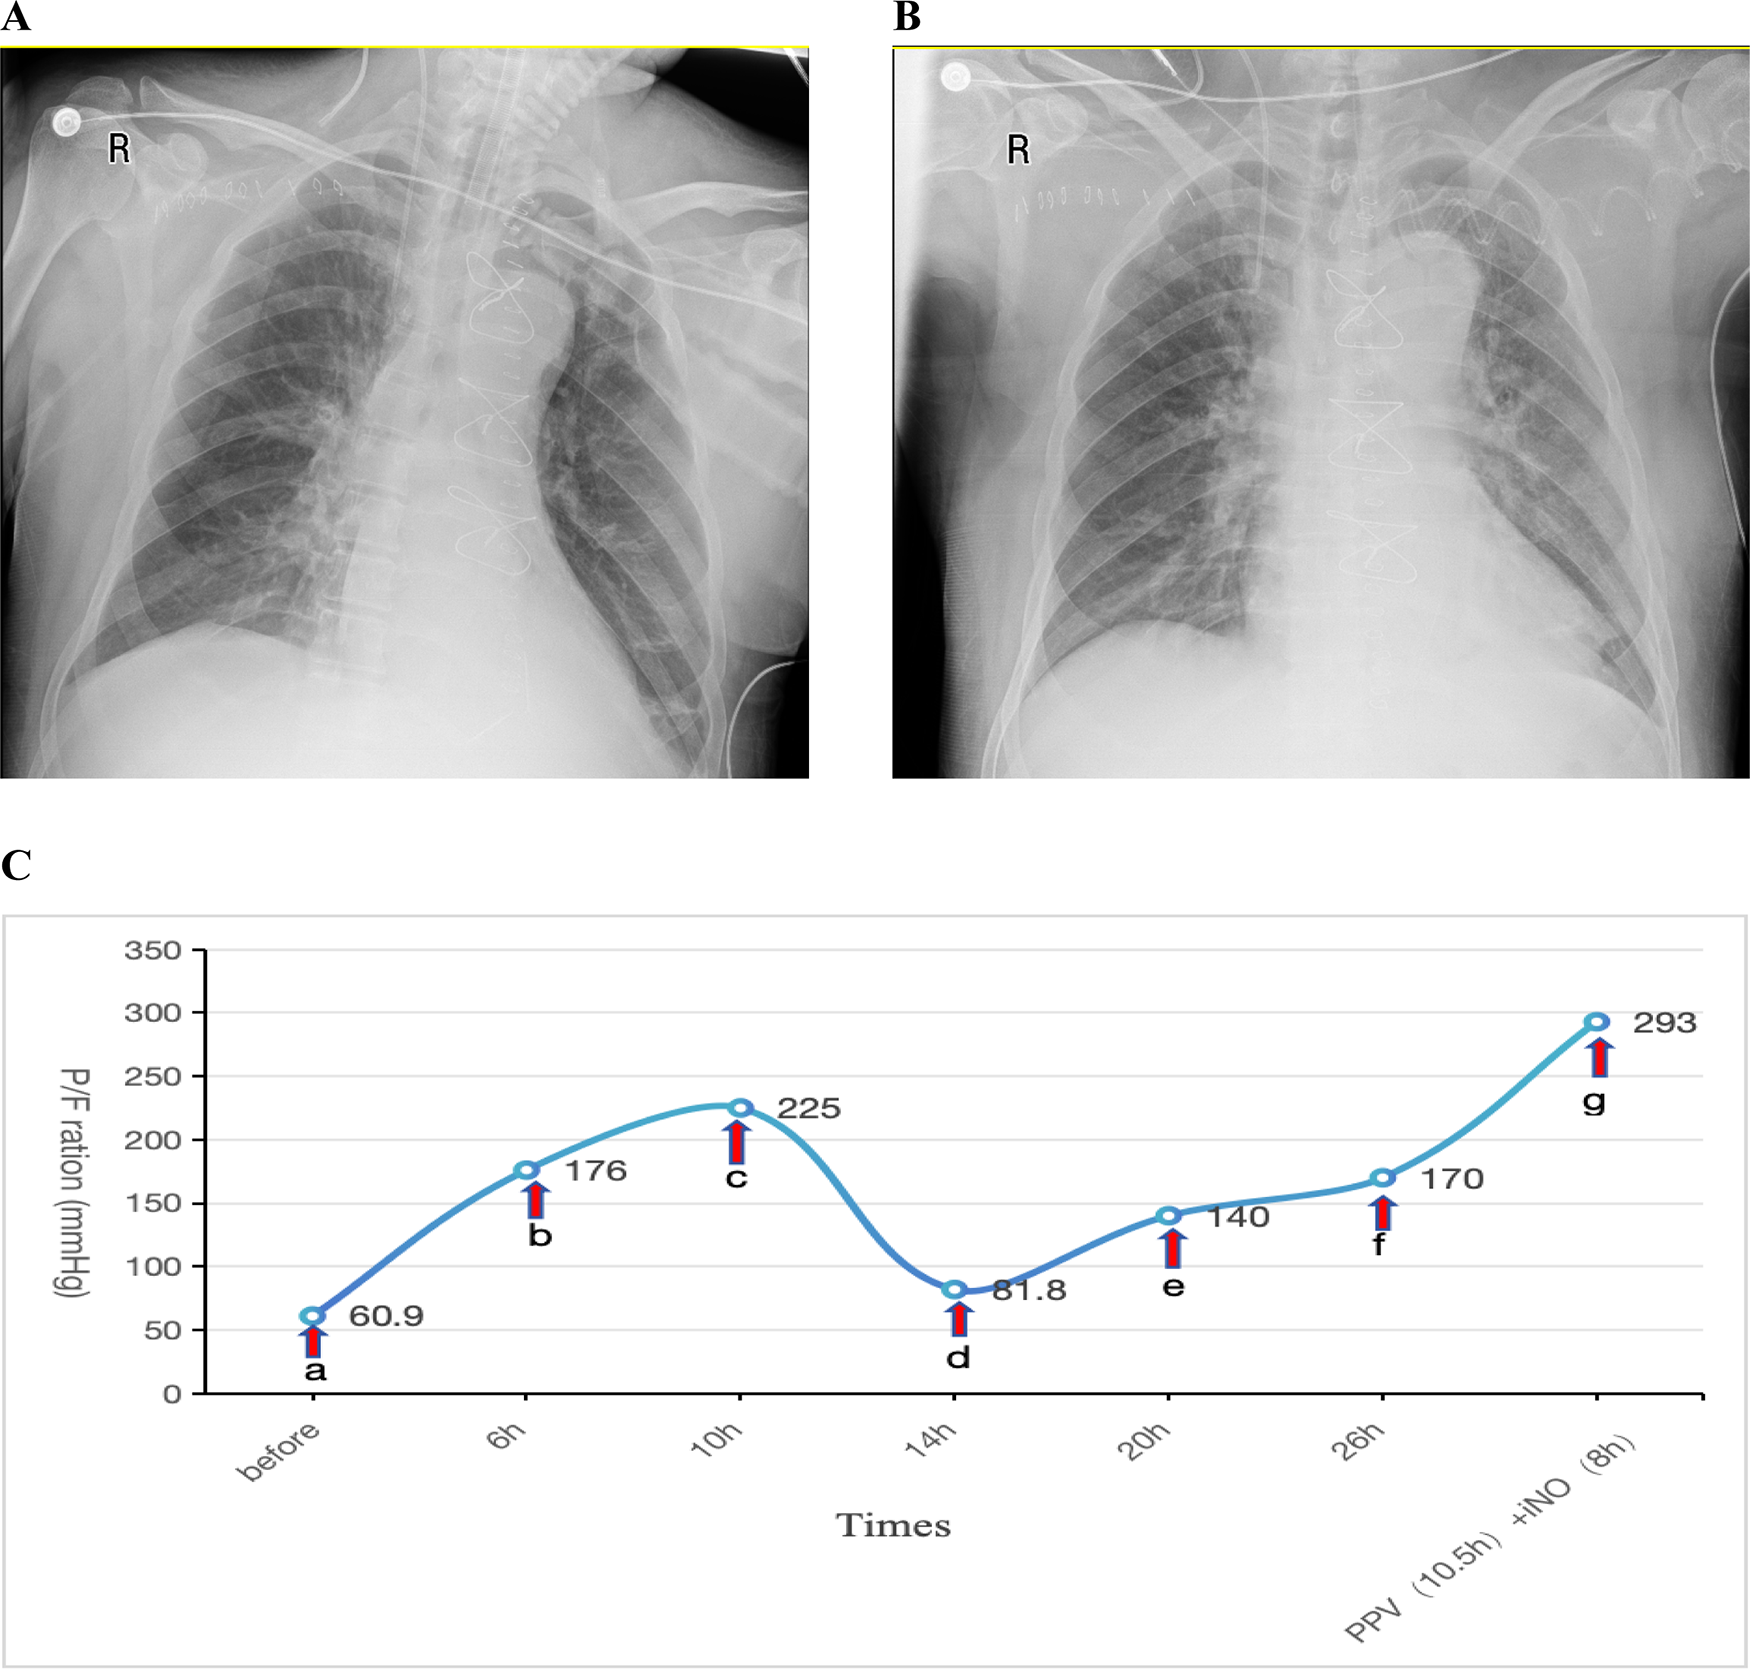

Postoperatively, the patient was transferred to the ICU with an initial P/F ratio of 183 mmHg and mild renal dysfunction (elevated serum creatinine). During the first two postoperative days, the patient maintained acceptable oxygenation. Therapeutic interventions included: Clindamycin 0.6 g bid for infection prophylaxis, Methylprednisolone 40 mg IV push once daily (qd) for anti-inflammatory management, Furosemide to maintain negative fluid balance.Ventilator settings remained elevated, with FiO2 fluctuating between 50%–80% and PEEP at 10–12 cmH2O. A spontaneous breathing trial (SBT) was attempted for weaning and extubation but failed. On postoperative day 3, oxygenation significantly deteriorated (P/F: 60.9 mmHg). A Chest x-ray showed a bilateral pulmonary infiltration (Figure 2A). Echocardiography indicated an LVEF of 57%, excluding cardiogenic pulmonary edema. This patient was also diagnosed with severe ARDS according the Berlin criteria.Despite conventional therapies mentioned above and the prophylactic antibiotic regimen was escalated to intravenous piperacillin-tazobactam (4.5 g q8h) for prevention of ventilator-associated pneumonia, refractory hypoxemia persisted. The patient remained hemodynamically stable with a heart rate of 70 bpm and blood pressure of 121/63 mmHg, maintaining circulation without vasoactive agents. The drainage output averages 20 ml/h. The patient also had no contraindications such as intracranial hypertension (ICH), unstable spinal fractures or sternal dehiscence with instability. So PPV was promptly conducted as the first-line therapy. Prior to PPV implementation given the early postoperative phase, we administered: Sedation: Midazolam to achieve RASS −3 to −5; Analgesia: Remifentanil infusion; Gut management: Enteral nutrition suspension >2 h, continuous gastric decompression during PPV. Concurrent safety measures: ①. Incision stabilization with thoracic binder; ②. Maintenance of drainage tube patency; ③. Endotracheal tube position verification; ④. Tracheal secretion suctioning. After 6 h of prone positioning ventilation, the P/F improved to 176 mmHg, further increasing to 225 mmHg at 10 h. INO was not administered concurrently at that time due to the significant oxygenation improvement achieved with PPV. However, upon returning to the supine positioning within 4 h, oxygenation declined again (P/F: 81.8 mmHg). Given concerns about potential wound complications from repeated PPV sessions within a short timeframe, iNO therapy was initiated at 10 ppm. Similar to Case 1, the imaging manifestations showed no significant changes on repeat chest radiography 2 days post iNo treatment (Figure 2B) in comparision with Figure 2A, but oxygenation progressively improved, reaching 140 mmHg at 6 h and 170 mmHg at 12 h after iNO administration. Subsequently, considering the potentially superior efficacy of PPV observed earlier, PPV was reintroduced, which resulted in a P/F increase from 104 mmHg to 161 mmHg after 10.5 h. As oxygenation significantly improved during PPV, iNO therapy was temporarily suspended during PPV sessions. Following prone session completion, iNO was resumed for 8 h, achieving a P/F of 293 mmHg (shown in Figure 2C).

Figure 2. (A) Chest x-ray obtained one day prior to iNO showing a bilateral pulmonary infiltration; (B) chest x-ray performed after 2 days of iNO therapy showing no significant changes; (C) changes in oxygenation index (P/F) before and after interventions at indicated timepoints. (a–c) PPV; (c,d) SPV; (d–f) iNO; (f,g) PPV (10.5 h), iNO (8 h). iNO, inhalation of nitric oxide; PPV, prone posioning ventilaton; SPV, supine posioning ventilaton.